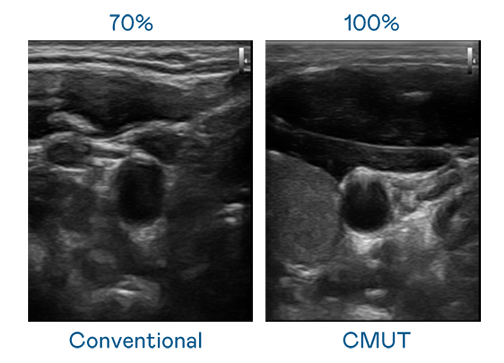

CMUT 技術是一種用電容式微機電元件來產生超音波訊號的技術。與傳統 PZT 壓電式技術相比,CMUT 頻寬增加 30%,更寬頻的超音波訊號讓影像解析度大幅提升,是實現高影像品質醫療超音波掃描、促進精準醫療發展的關鍵技術。

超音波影像的解析度高低,首先取決於探頭能發出的訊號頻寬。梦之城 CMUT 可提供高清晰的超音波訊號,提供高頻寬、高靈敏度、影像紋理細節更高的超音波影像,協助醫護人員縮短影像判讀時間及利用精準的醫療影像進行診斷。